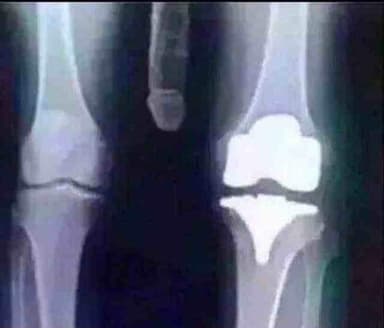

Knee! I've had both of mine done!

knee replacement thats the kneecap

Knee cap

Looks like the prosthetic component for the medial condyle of the femur and it’s quite possible that it’s part of a Total Knee Arthroplasty.

This is a partial knee joint replacement. I help put them in everyday except Friday Saturday and Sunday..Upper part.

Looks like implant for knee replacement. You don't realize the stress you put on your knees, until they start mocking you with every step.